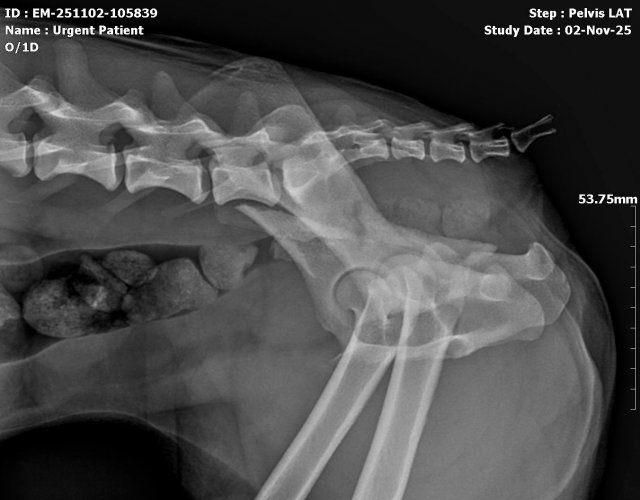

Caine accidentat

O doamna a gasit un caine lovit de masina si l-a tras pe marginea drumului pentru a suna peste tot in cautare de ajutor. Am raspuns pozitiv si am facut totul pentru el. Din pacate nu a putut fi salvat, decedand a doua zi dupa interventia chirurgicala. Foarte probabil din cauza unei embolii pulmonare. Le multumim celor care au donat. Medicul a anulat factura iar banii vor ajuta desigur alte animale de care ne ocupam zilnic.